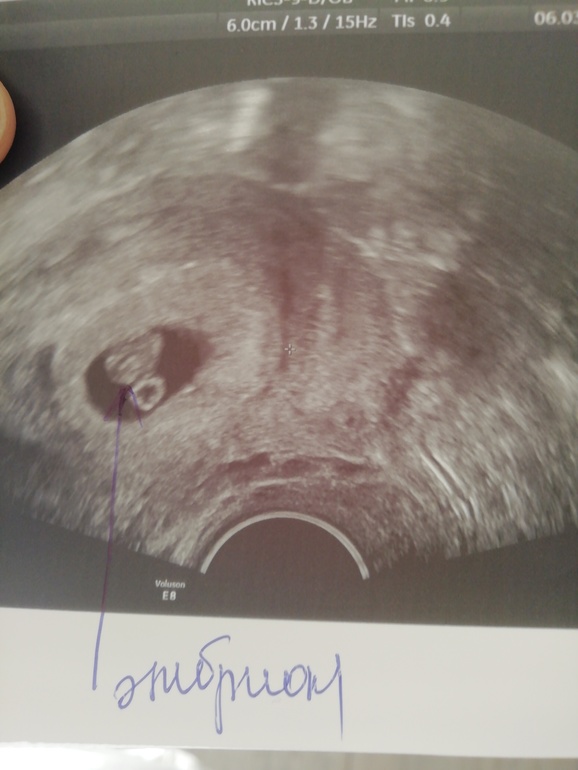

Марина Мищенко

Здравствуйте,пост вижу старый но всё же может ответить,могли бы вы посмотреть по УЗИ кто будет

12.10.2021